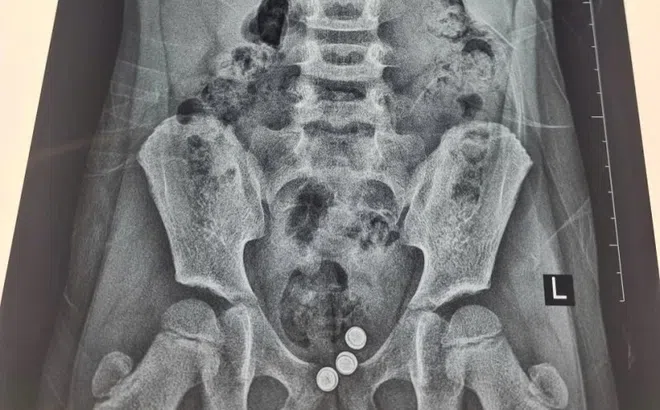

Bé gái chảy dịch âm đạo kéo dài vì nguyên nhân khó ngờ

Các bác sĩ vừa can thiệp, lấy ra ba viên pin từ vùng kín một bé gái 5 tuổi. Dị vật đã gây viêm đỏ và tổn thương âm đạo của trẻ.